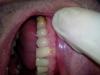

dantist-ya Опубликовано 14 мая, 2013 Поделиться Опубликовано 14 мая, 2013 (изменено) Всем доброго времени суток!!! Помогите с планом лечения. Пац уезжает в Австралию на пмж, приехать сможет как минимум через три года. КД очень глубокий, поражены все зубы,какие то меньше,другие больше. Прикус ортогнатический. За качество фото извиняйте,фотал на телефон.Стоит ли одевать коронки на эти зубы? Или же пока эндодонтия ,реставрация и в добрый путь на 3 года? Работаю без кофера,а кд уже под десной. Изменено 14 мая, 2013 пользователем dantist-ya Ссылка на комментарий

johniola Опубликовано 15 мая, 2013 Поделиться Опубликовано 15 мая, 2013 дайте фото в прикусе. я думаю что здесь вариант коронки.имхо Ссылка на комментарий

dantist-ya Опубликовано 15 мая, 2013 Автор Поделиться Опубликовано 15 мая, 2013 Всем большое спасибо за ответы.Об устранение рецессии хирургическим путем можно забыть. Пац не потянет финансово. Выбирать нужно их двух ЗОЛ-эндо ,коронка либо эндо реставрация. Завтра выложу ОПТГ . Только вот за качество переживаю за ранее,нет фотика,только на телефоне. Ссылка на комментарий